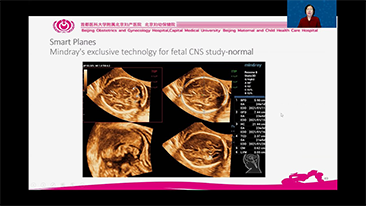

Geburtshilfe